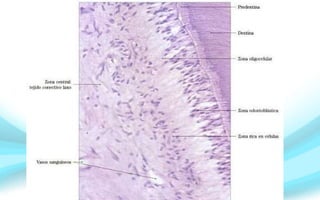

Zonas topográficas de la pulpa.

Se identifican

desde la

predentina

hasta la pulpa

Zona

odontoblástica.

Zona subodontoblástica

u oligocelular de Weil.

Zona rica en

células.

Zona central de la pulpa o

tejido pulpar propiamente

dicho.

Zona odontoblástica.

Está constituida por los odontoblastos, celulas

subodontoblasticas de Höhl.

Los cuerpos celulares de los odontoblastos se

conectan entre sí por diferentes complejos de

unión, en la porción proximal (vecina a la

predentina) se destaca la presencia de uniones

ocluyentes y desmosomas.

• En las caras laterales predominan las

uniones comunicantes de tipo hendidura o

gap.

Zona subodontoblástica u

oligocelular de Weil.

• Tiene aproximadamente 40 µm de ancho.

• Zona pobre en células.

• Está bien definida en la región coronaria de los dientes recién

erupcionados, pero, suele estar ausente en la región radicular. En

pulpas maduras la capa oligocelular alcanza un espesor de 60µm.

Se identifican:

1.- El plexo nervioso de Raschkow.

2.- El plexo capilar subodontoblástico.

3.- Los fibroblastos subodontoblásticos.

Zona rica en células.

Se caracteriza por su alta

densidad celular.

• Destacan las células

ectomesenquimáticas.

• Células madre de la pulpa.

• Los fibroblastos que

originan las fibras de Von

Korff.

Zona central de la pulpa.

Está formada por el tejido

conectivo laxo, característico

de la pulpa.

Con sus distintos tipos

celulares, escasas fibras

inmersas en la matiz

extracelular amorfa y

abundantes vasos y nervios.